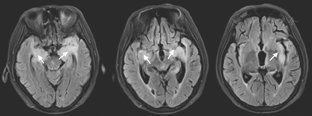

患者女性,72岁,主因渐进性右肢力弱9个月、记忆力减退3个月、错认1周于2015年6月17日入天津市环湖医院。患者于入院前9个月渐感做家务时右手无名指、小指力弱,遂就诊于天津市某综合医院,行头颅CT检查(图1),考虑脑梗死,给予输液治疗2周,此症状渐进性加重,累及中指及右手。于入院前3个月,患者因右手持物力弱、右下肢行走无力、记忆力减退、近期发生过的事情记不起来,再次就诊于天津市某中医医院,行头部MRI检查(图2),FLAIR序列可见双侧颞叶内侧面、海马区高信号影。按照脑梗死给予输液治疗,并口服阿司匹林、阿托伐他汀治疗。于入院前1周,患者右肢无力较前加重,右手持物不稳,右下肢站立及行走需搀扶,并数次跌倒。家属发现其偶有面孔错认,把自己的亲人认错。为进一步诊治收入院。自发病以来,患者无明显头痛及头晕,无视物旋转及视物成双,无恶心呕吐,无耳聋耳鸣,无肢体麻木及抽搐,无意识障碍,存在情绪低落、兴趣减少、食欲下降,体重3个月内减轻5 kg。既往史:有高血压病史20余年,血压最高达160/100 mmHg (1 mmHg=0.133 kPa),平时口服缬沙坦80 mg (1次/d)降压治疗,血压维持在120~130/90 mmHg。入院后神经科体检:意识清楚、构音障碍,双瞳孔等大等圆,光反射(+),眼动可,眼位居中,无眼震及复视,右侧鼻唇沟稍浅,伸舌尚居中,颈软,右肢肌力Ⅳ级,左肢肌力Ⅴ级,肌张力可,腱反射(++),双侧巴宾斯基征(-),右面部及右侧肢体浅感觉异常,双侧共济检查稳准。高级神经活动认知功能检查:简易精神状态检查评分12分,蒙特利尔认知评估量表评分7分,定向力、回忆能力、计算力、语言重复流畅性、执行功能、视空间结构等领域均受累。实验室检查阳性结果:血常规示中性粒细胞百分比83.0%(正常值40%~75%),血小板计数68×109/L[正常值(125~350)×109/L];红细胞沉降率37.00 mm/h(正常值0~15 mm/h),乳酸脱氢酶265 U/L(正常值135~225 U/L];甲状腺功能全项:三碘甲状腺原氨酸1.00 nmol/L(正常值1.3~3.1 nmol/L);血液三项:叶酸4.08 ng/ml(正常值4.6~34.8 ng/ml)。超敏C反应蛋白、乙型肝炎、梅毒血清学检查结果正常。肺癌和肝脏、胃肠、盆腔肿瘤标志物检查结果正常。入院后行腰椎穿刺检查,压力200 mmH2O(1 mmH2O=0.009 8 kPa);脑脊液常规:总细胞数382×106/L,白细胞数2×106/L[正常成人(0~8)×106/L] ;脑脊液生化:氯化物117 mmol/L(正常值120~132 mmol/L],蛋白1.18 g/L(正常值0.15~0.45 g/L),乳酸5.4 mmol/L(正常值0.6~2.2 mmol/L)。脑脊液免疫功能:白蛋白714.00 mg/L(正常值0~350 mg/L),免疫球蛋白A 6.89 mg/L(正常值0.1~5 mg/L),免疫球蛋白G 56.30 mg/L(正常值0.1~34 mg/L),免疫球蛋白M 2.68 mg/L(正常值0~1.3 mg/L)。脑脊液病理检查可见大量红细胞及少量单核细胞、淋巴细胞。入院后查头颅MRI(2015年6月18日;图3)示双侧岛叶、双侧海马FLAIR高信号(较3月前增大)。增强头颅MRI(2015年6月19日;图4)示双侧颞极、双侧海马、双侧岛叶轻度肿胀,伴异常信号,增强后未见明显异常强化。胸片示主动脉硬化,腹部超声示肝胆胰脾未见明显异常。胸部CT、肝胆胰CT未见异常。盆腔CT示双侧附件区点状钙化影,考虑输卵管钙化。泌尿系超声未见明显异常。肌电图提示:右上肢(颈6~8)神经源性损害,重频电刺激未见明显异常。脑电图提示:清醒及睡眠脑电图各导联可见较多散在低中幅不规则慢波,以前头部为著,未见痫样波发放。副肿瘤相关抗体检查:血及脑脊液双份抗Ma2抗体检测,血为阳性(++),脑脊液阴性;抗神经元胞核抗体(Hu-Ri-Yo)、抗塌陷反应调节蛋白5(cV2)抗体、抗双载蛋白(amphiphysin)抗体阴性;N-甲基-D-天冬氨酸(NMDA)受体抗体、谷氨酸α-氨基-3-羟基-5-甲基-4-异